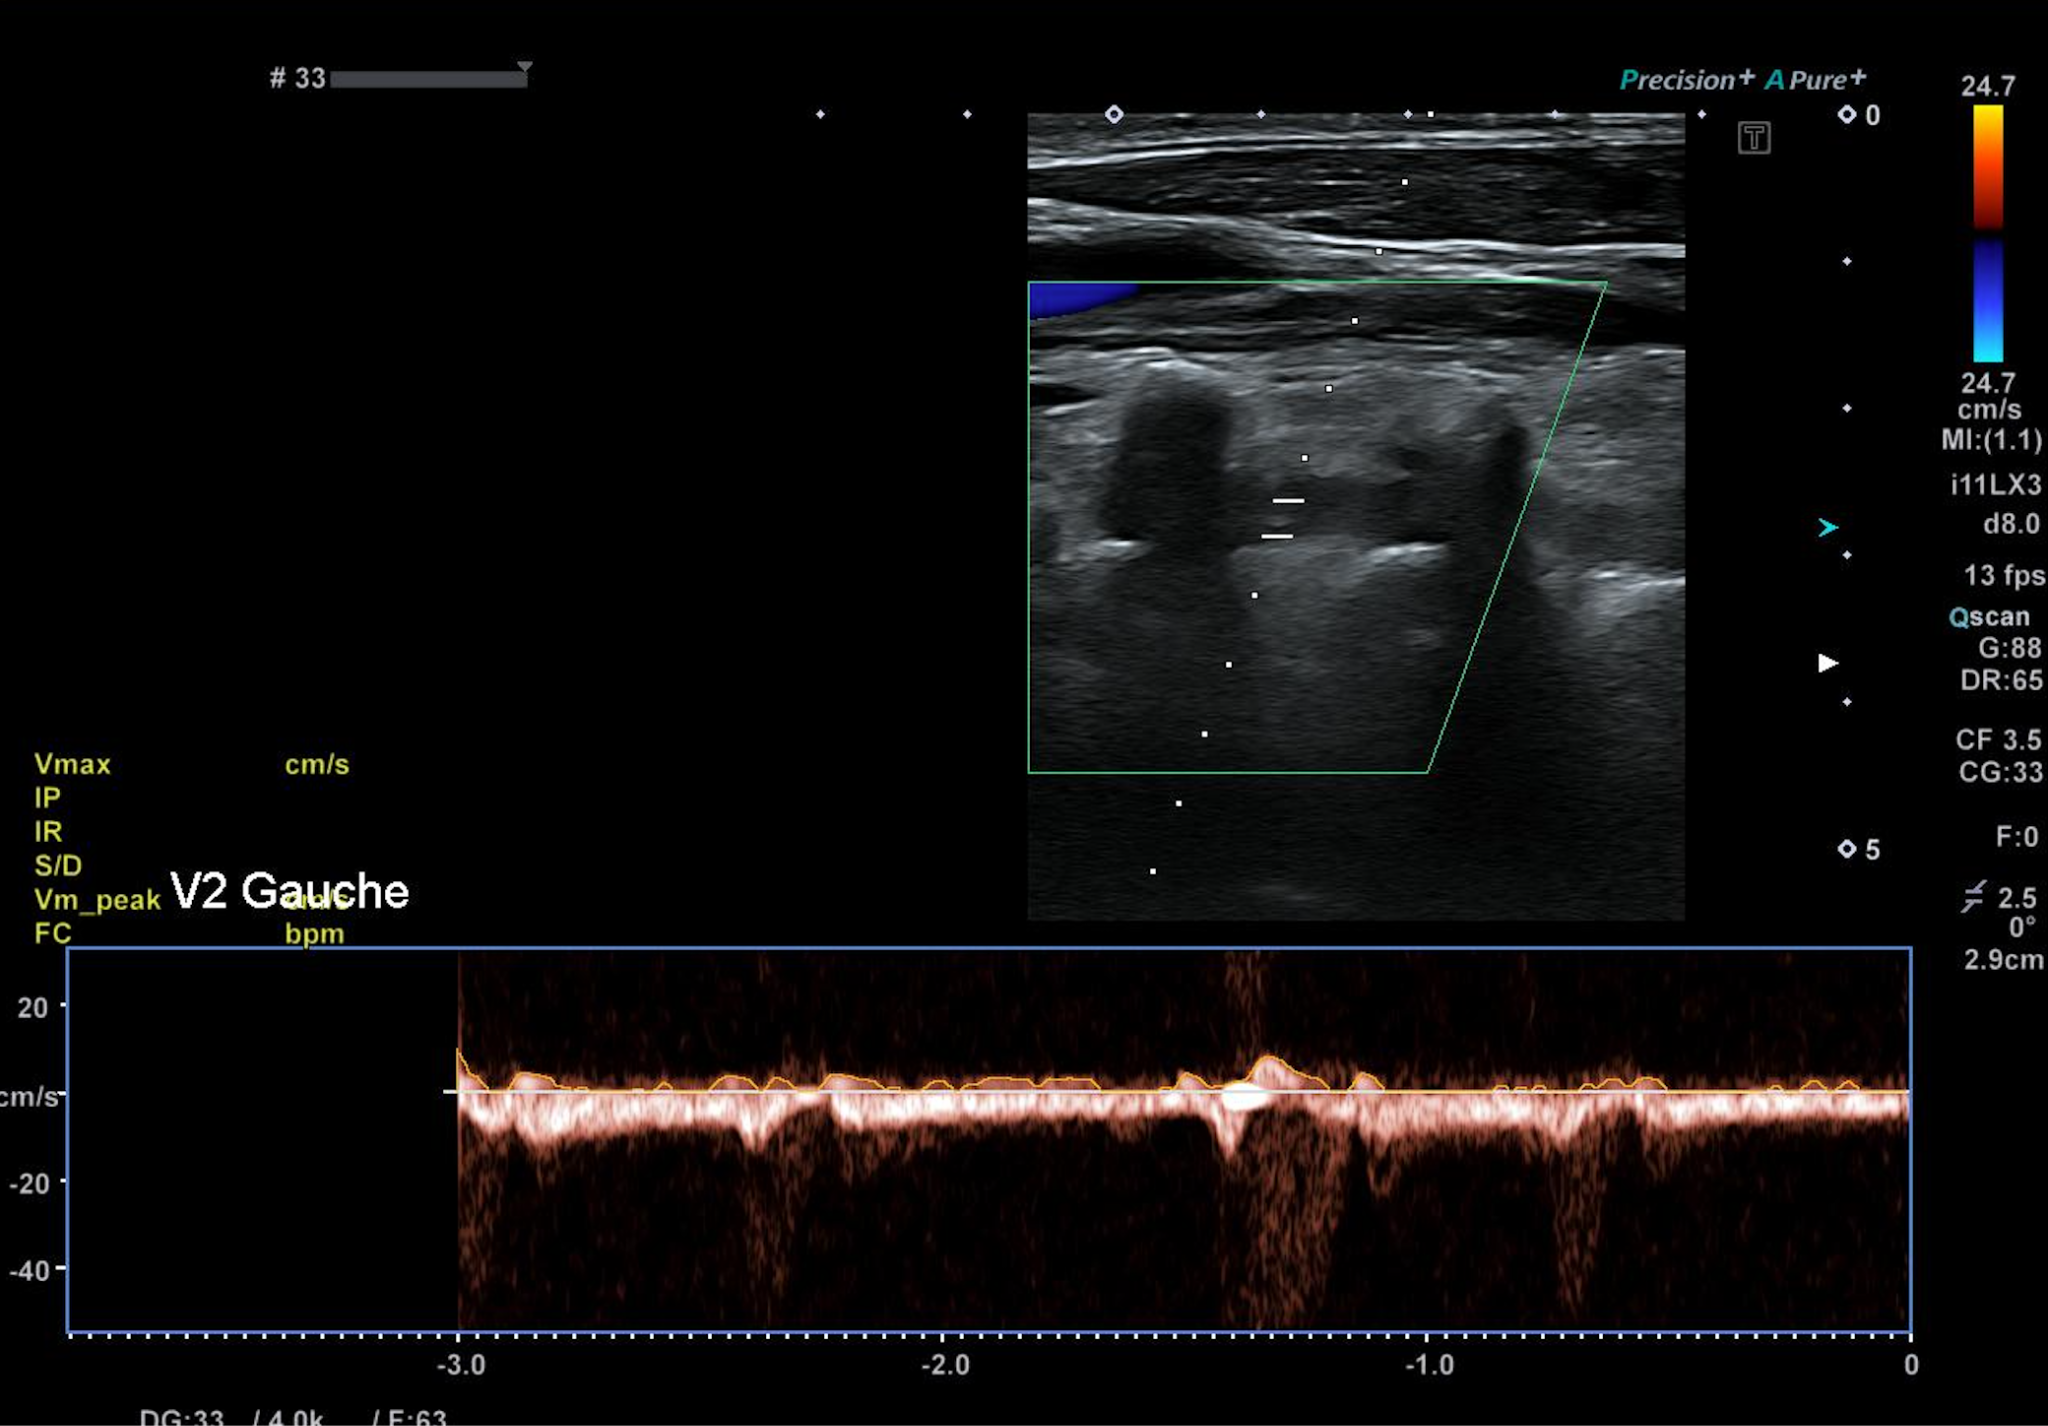

Il existe cependant un retentissement sur l’artère vertébrale gauche, avec un vol vertébro sous clavier intermittent : inversion uniquement du flux systolique.

Dans les cas plus évolués, l’inversion est systolo diastolique (vol permanent).